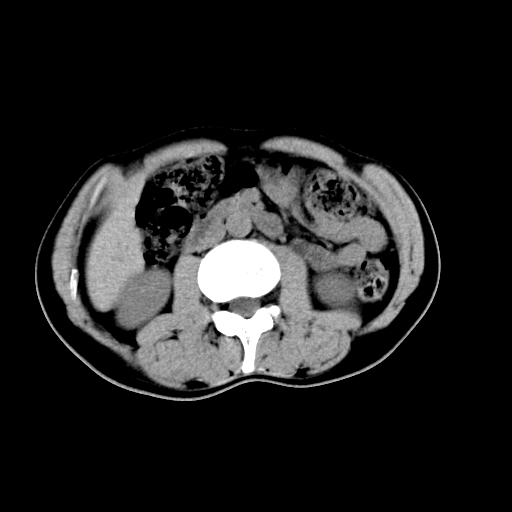

男,47岁,左输尿管结石碎石治疗后10余日。彩超示:左输尿管下段狭窄、输尿管积水。请各位讨论一下左输尿管下段结石还是静脉石?

象是第二狭窄处结石伴以上输尿管、肾盂轻度积水。

输尿管结石伴以上输尿管、肾盂轻度积水。

两侧髂总动脉壁斑状及点状钙化.左侧输尿管行经与左髂总动脉相交后见高密度影,且下段输尿管管腔未见扩张,应该要考虑结石伴以上输尿管及肾盂积水.但右侧结节状高密度影,也应该是结石吧!那以上输尿管未见扩张呢!因此静脉结石可能性也较大.请问楼主碎石前左侧输尿管结石位置.

虽左侧有轻度肾盂积水但不支持结石。1结石边周应该有软组织包绕呈晕征。2钙化点前面见输尿管影也不支持是结石。3彩超没提结石。建议超生复查。

输尿管先位于腹部,后进入盆腔,最后斜穿膀胱壁开口于膀胱,因此,临床上常将输尿管分为腹段、盆段和壁内段。第1个狭窄:在肾盂与输尿管移行处。第2个狭窄:在跨过髂血管处。第3个狭窄:在穿过膀胱壁处。这些狭窄是结石容易滞留的部位。

左侧输尿管有轻度扩张伴有肾盂积水,输尿管下段周围的高密度影不象在输尿管内。

同意,不支持结石。(因显示该高密度影前见扩张输尿管影,另外两侧对称显示)。

左侧高密度影在左侧输尿管的内侧方,所以不考虑输尿管结石.

我认为不是结石的可能性大,因为他的位置和血管钙化的位置邻近